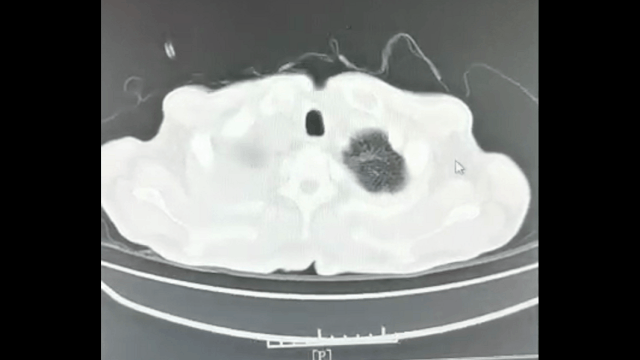

4月15日查胸部CT示:右肺下葉段空洞樣病變,右肺中葉大片炎癥,社區(qū)調(diào)整為左氧氟沙星+氨曲南抗感染治療,后仍無明顯好轉(zhuǎn)。

經(jīng)過半個月治療后5月18號復(fù)查胸部CT平掃,提示肺膿腫較前明顯好轉(zhuǎn),胸腔積液明顯減少。

圖1:患者肺部CT動圖